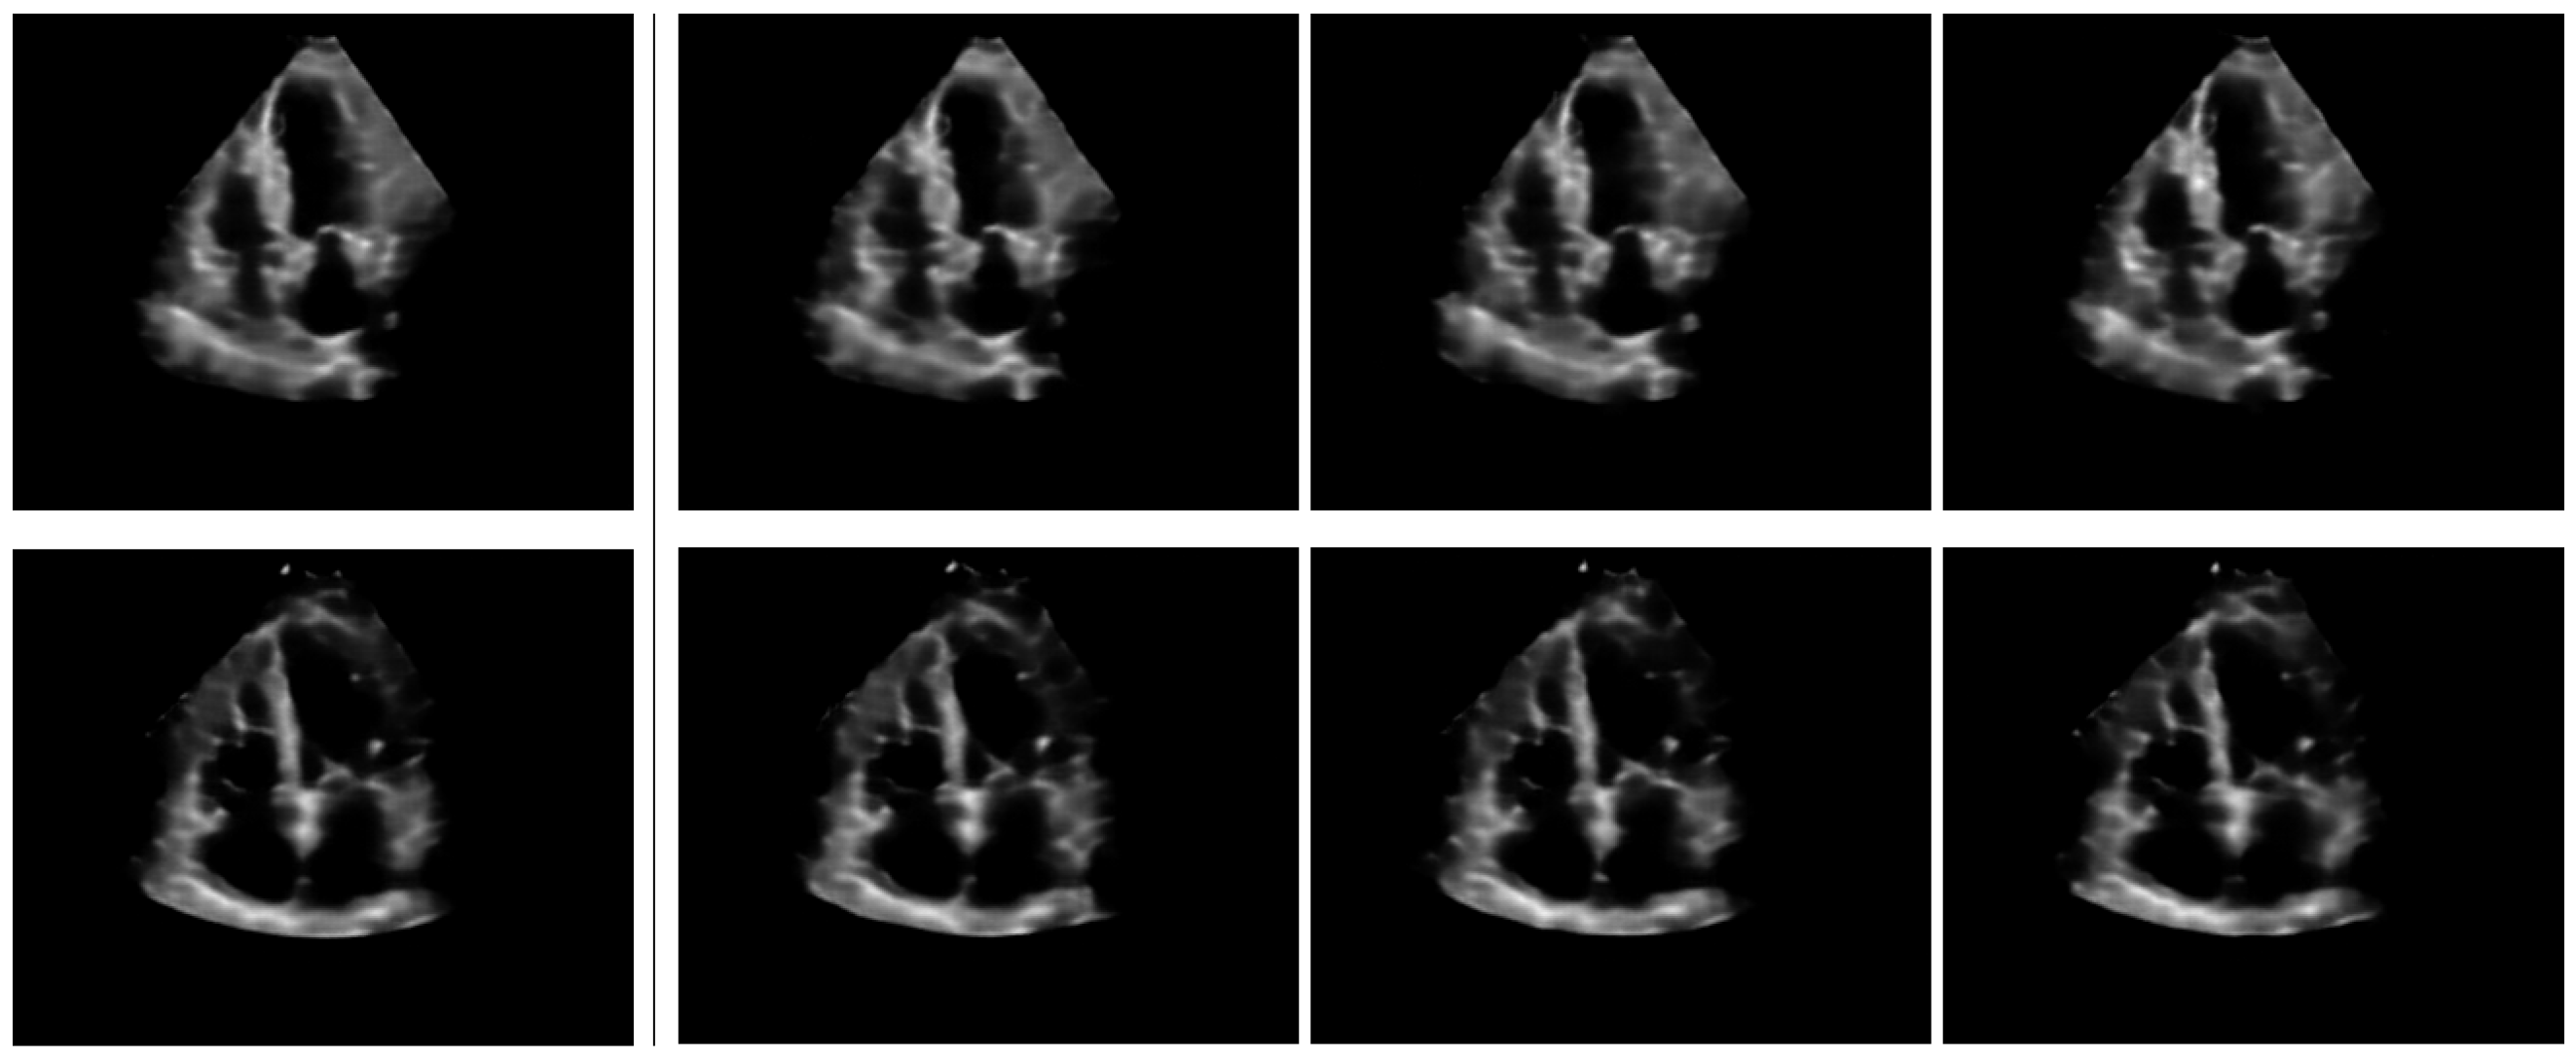

Upon convergence, the pre-trained model can be qualitatively analysed by examining the inferred concept probability maps for test images. A straightforward method to implement this involves selecting the most likely concept at each grid location () and overlaying the up-sampled concept indices grid onto the initial input images, as in Figure 3. The probability of the most likely concept at each location can be incorporated in the visualisations.

Figure 3.

Concept maps for three randomly sampled inputs. The 16×-stride concept grid is up-sampled to the original image size. The indices of the most likely concept for each grid location are displayed in red at the bottom-left of each location. The grid is color-coded according to concept indices for better visualisation.

By examining a random selection of samples illustrated in Figure 3, we can make the following initial observations:

- The prior constraint, which requires regions outside the cone to be modeled solely by the first concept (i.e., the background concept at index 0) is generally respected. Exceptions occur at grid locations in the cone’s proximity, particularly at the boundaries between the cone and the background. As these are transition regions, they are not particularly concerning, since the model’s confidence is expected to be low for such regions.

- Certain concepts are specialized for specific anatomical structures. For example, concept models blood pools within the cone, concept represents the Left Ventricle (LV) free wall on the right hand size of the cone, concepts and correspond to septum walls, and concept covers the right-heart side of the cone, among others.

- Certain concepts, such as e.g., and appear more isolated and spanning a single grid location. By qualitatively assessing multiple input samples, we hypothesise these concepts encode information about the local anatomical shapes of nearby larger concept islands. It appears these concepts have larger confidence assigned to them than the average confidence inside larger concept islands. We term them modifier concepts.